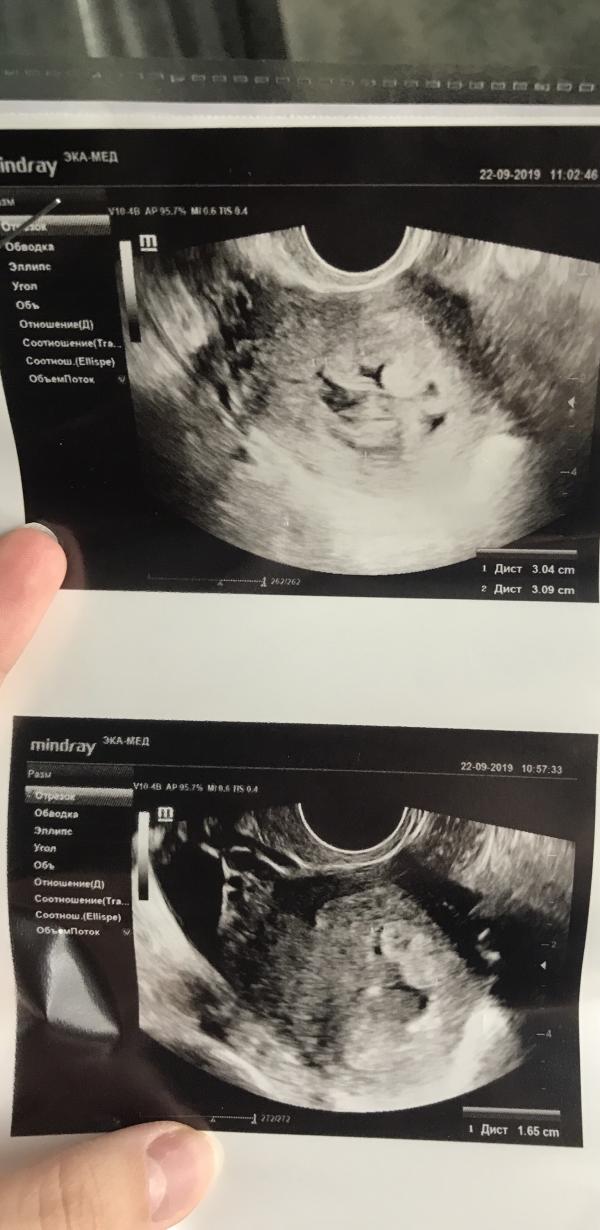

Девочки привет. Сегодня была на УЗИ. Врач, по непонятно объяснённым мне причинам поставила ЗБ. Срок 7н2дня. Все размеры соответствуют срокам. Ей не понравилось, что нет сердцебиения и что что-то не так там располагается как должно быть. Насколько я знаю сердцебиение может появится и позже. А вот сами снимки узи мне показались странными, ни у кого таких не видела. Думаю сделать УЗИ в другом месте.

@marus9, да тоже соглашусь с вашим ощущением про увеличение... обычно никто не увеличивает - иначе помехи будут ( ну это я так понимаю, я конечно не специалист...). Посмотрела по значениям - ктр 15 мм соответствует 8 неделям... тогда и срок она не правильно пишет... как мне говорили - самое точное узи по определению срока - именно начало беременности, потому что примерно у всех развивается эмбрион одинаково. Думаю, ошиблась она.. Переделайте, конечно..

На снимке не понятно ничего ..обычно шарик,а в нем точечка 🤷♀️🤷♀️

На нижнем снимке как я понимаю эмбрион справа. Такое ощущение, что увеличение раз в 20, но зачем 🙈